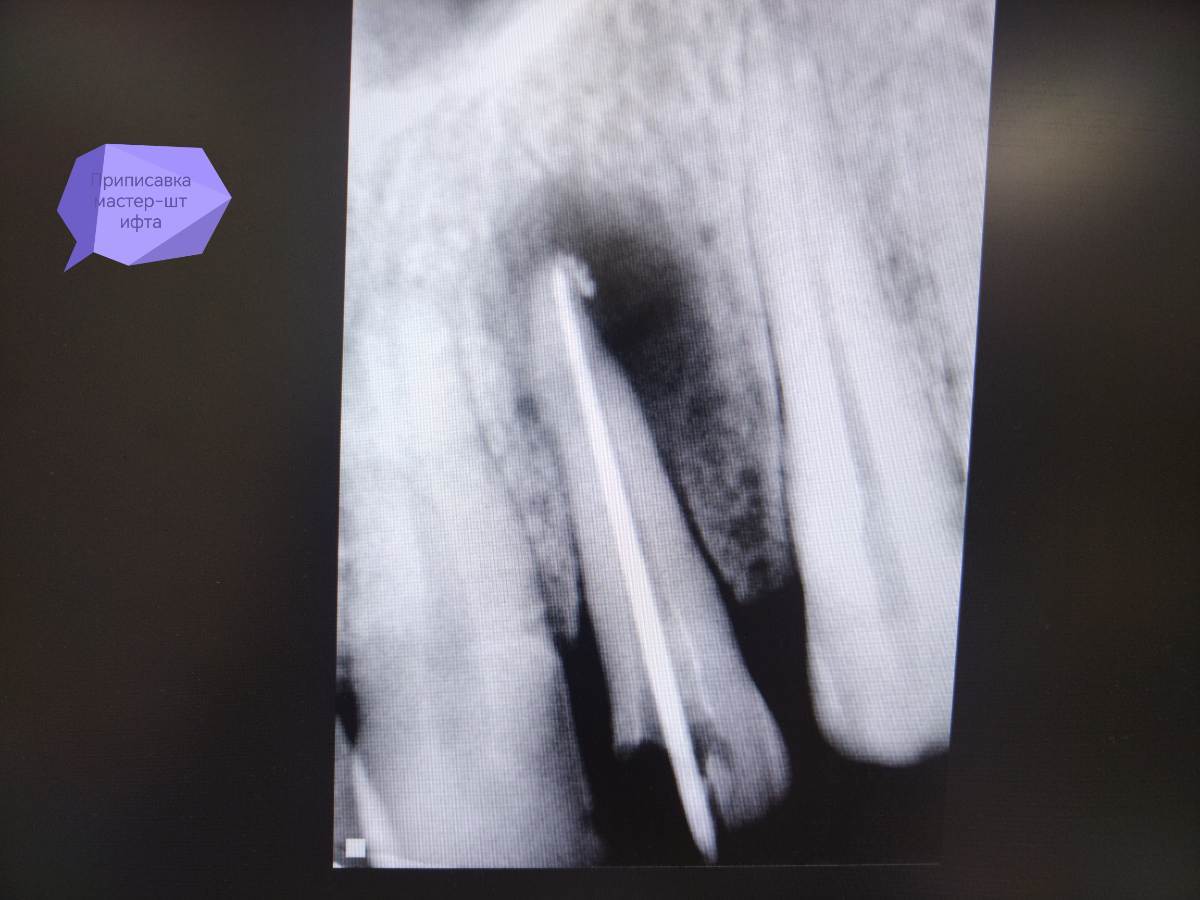

АВА2018 Опубликовано 28 декабря, 2025 Поделиться Опубликовано 28 декабря, 2025 Цитата Добрый вечер, коллеги 🙂Оцените, пожалуйста, качество пломбирования зуба 22 и есть ли перерасширение устьевой части канала.... Протокол работы: В 1 посещение-Механическая и медикаментозная обработка канала ручными к-файлами до 45 размера , промывание 3% раствором паркана, ЭДТА, активация эндоактиватором, вода. Изначальный размер канала 25 размер к -файла....Высушивание, получен экссудат в небольшом количестве. Временная пломбировка кальсептом на 2 недели. 2 посещение-Жалоб нет. Снятие пломбы, вымывание кальция из канала 3 % раствором паркана, водой дистиллированной. Долго не могла вымыть кальций из канала, при активации эндоактиватором выходили стружки кальция.... Постоянная пломбирование пастой Н+ с гуттаперчевыми штифтами методом латеральной конденсации. Пациенту придёт через 6 месяцев для контроля заживления.. Ссылка на комментарий

АВА2018 Опубликовано 28 декабря, 2025 Автор Поделиться Опубликовано 28 декабря, 2025 Скажите, пожалуйста, есть ли перерасширение цервикального дентина? Я работала без устьевика... Но на снимке отчётливо вижу перерасширение... Да и вообще проблема у меня с вымыванием кальция из каналов , я не могу понять, вымыла ли я его полностью, всё равно идёт белая стружка при активации. Я потом беру мастер-файл и н-файл по стенкам вожу и всё равно идёт белая стружка... Есть вообще ощущение, что я каналы перерасширяю.... Фанатизм мой до добра не доведёт... 😩Переживаю ща пациента.... Ну вот это перерасширение или просто ракурс такой? Ссылка на комментарий